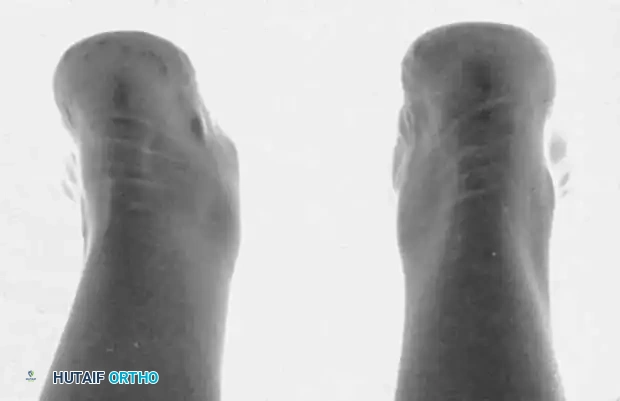

Fig. 79-8 Elongated cornuate navicular (Type III).

Fig. 79-7 Accessory navicular. A, Teenage girl with prominent symptomatic accessory navicular. B, Large accessory navicular.